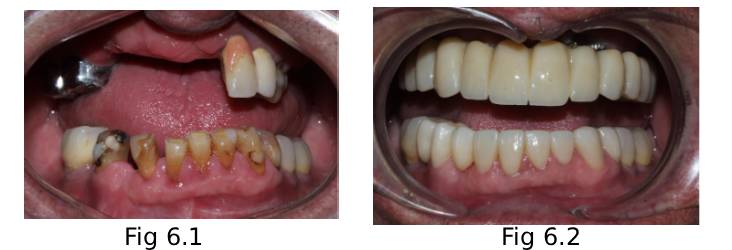

Before & After

Before treatment (Fig 6.1) After treatment (Fig 6.2)

Worn-out, stained and failing teeth Illusion Zirconia Dental Bridge has lifelike aesthetics. This gives not only a natural look but feels comfortable as well.

Missing back teeth Fully fixed teeth in both arches.

Poor facial structure The vertical dimension was fixed. This restored the sunken facial appearance.

Unable to chew properly Patient could eat everything with confidence.